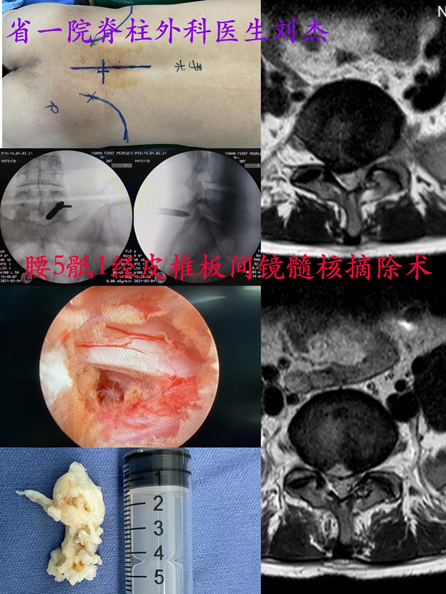

我们知道,椎间孔镜手术是通过侧方穿刺进入椎间孔,它适用于大多数节段的腰椎间盘,但是人体解剖结构不同,部分患者侧方髂骨较高,有时椎间盘突出的位置靠中央,尤其是在腰5骶1节段,从侧方穿刺可能无法准确的进入椎间孔,或者即使进入了椎间孔也可能不能完全取出偏中央突出的髓核组织,同时腰5骶1椎板间隙较宽有利于穿刺,因此在腰5骶1节段的椎间盘突出,经椎板间隙进行手术,优势较经椎间孔手术更为明显,也正是因为上述原因,目前经椎板间隙内镜手术主要用于腰5骶1椎间盘突出。

下面我们通过一个具体的病例,来展示一下经椎板间隙脊柱内镜腰椎间盘髓核摘除术是怎么做的

首先手术麻醉采用的是全身麻醉,和椎间孔入路不同,椎板间隙入路在术中可能需要对神经根进行牵拉、分离粘连等操作,在局麻下往往会引起明显的不适。因此选择全麻会让手术过程中患者的舒适性更高,同时全麻下的手术操作也是非常安全的。

麻醉成功后医生和护士会将患者摆放成俯卧位,在C臂透视辅助下进行腰5骶1椎板间隙的穿刺定位,定位准确后沿着导丝经椎板间隙放入扩张管道,这种逐级扩张的操作对于肌肉的损伤很小、出血也很少,同时经椎板间隙入路也不需要切除正常的骨质;

随后经扩张管道放入工作通道,然后在内镜直视下只需在黄韧带上开一个小口,即可将工作通道进一步置入椎管内;直视下辨识硬膜囊、神经根和突出的椎间盘组织,用髓核钳等工具摘除突出的椎间盘组织,手术即告完成。

通常手术切口大约在8mm,出血一般都很少,多数不到10ml;仅切除少部分黄韧带,对脊柱的稳定性和正常活动功能没有任何影响。